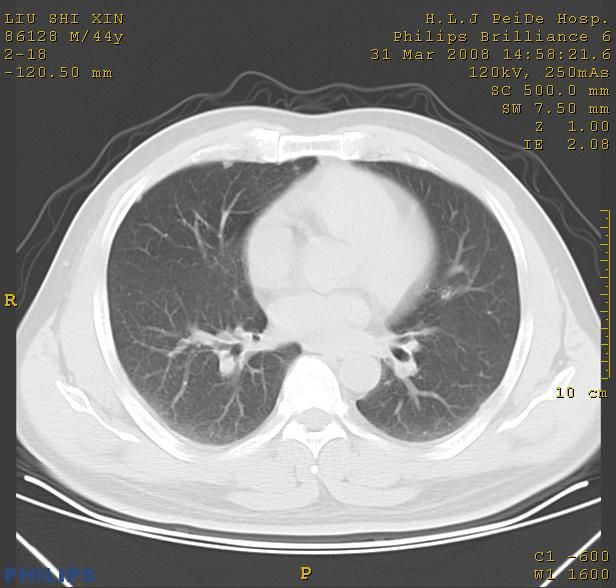

标题: CT13096:请分析胸膜下结节的影像基础是什么 有病理结果 [打印本页]

标题: CT13096:请分析胸膜下结节的影像基础是什么 有病理结果

瘢痕挛缩,胸膜牵拉,血管纠集扭曲,上叶前段支气管显示欠清,周围散在斑片影,以纵隔旁肺癌可能性大。请穿刺检查。

中心型肺癌并阻塞性肺炎及肺内转移

中心型肺癌并阻塞性肺炎、两肺及胸膜多发转移。

结节灶与血管末梢相通象转移灶;小三角状尖部有纤维索是胸膜拉扯征;纵隔旁大片实性影有点状钙化;周围有名显纤维瘢痕征可考虑瘢痕癌

本病例有病理结果是,鳞状上皮癌,胸膜下结节影病现诊断的肿大淋巴结,谢谢大家分析,请问胸膜下结节是肿大淋巴结怎么解释